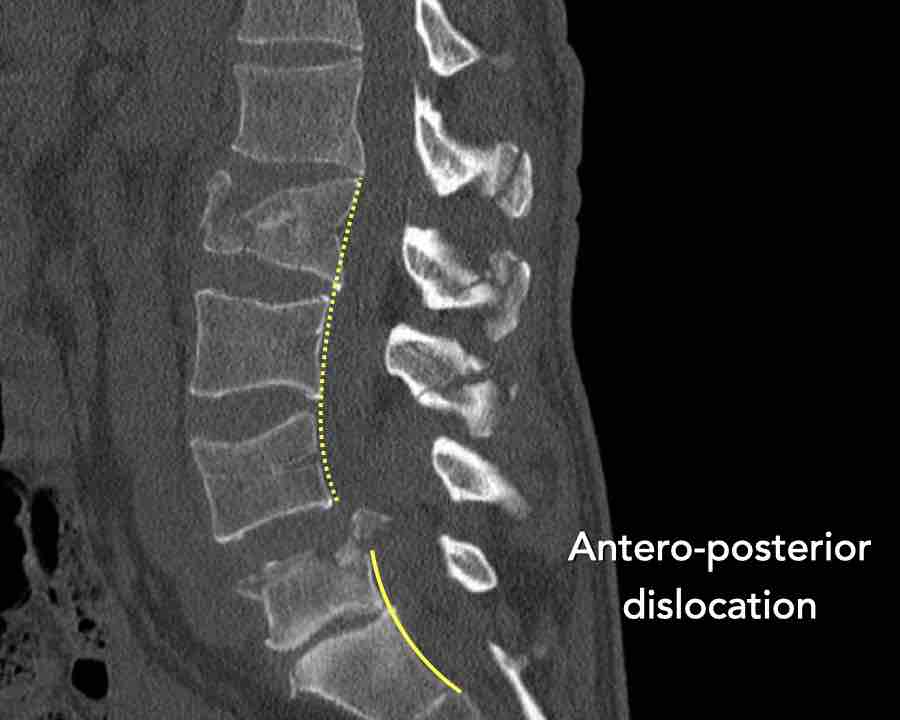

Type C Translational injuries

We start with the most severe injury and work from there.

Translational injuries are dislocation or displacement of a vertebral level from the level below or above.

There are no subtypes because various configurations are possible.

There is a high degree of instability and therefore an indication for surgery.

Images

This is a clear example of translation in the anterior direction.

Conclusion

Type C injury.